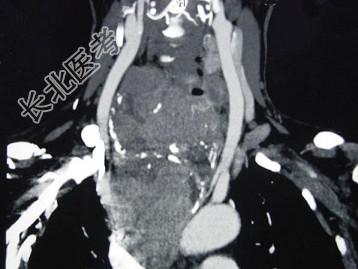

- 多项选择题女,48岁, 颈部包块3年,近来胸闷、憋气、胸痛, CT扫描如图,正确的描述或诊断是 ( )

A、胸骨后甲状腺肿

C、双侧甲状腺肿大

D、胸骨后甲状腺肿是指甲状腺50%位于胸骨后

E、胸骨后甲状腺肿是指甲状腺60%位于胸骨后